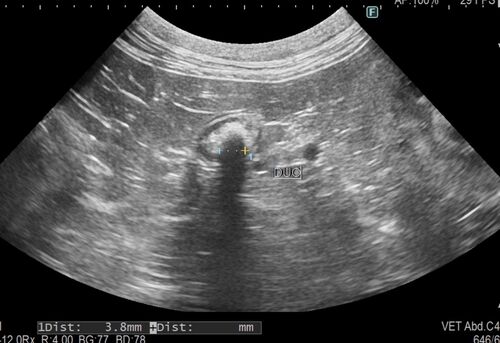

皆様こんにちは。 今回は、健康診断プレミアムコースにて、左の尿管結石が認められた猫ちゃんです。レントゲンでは後腹膜エリアに結石の陰影が確認され、超音波検査では腎臓の腎盂が拡張しており、尿管結石による尿路閉塞で水腎症になっていました。 血液検…